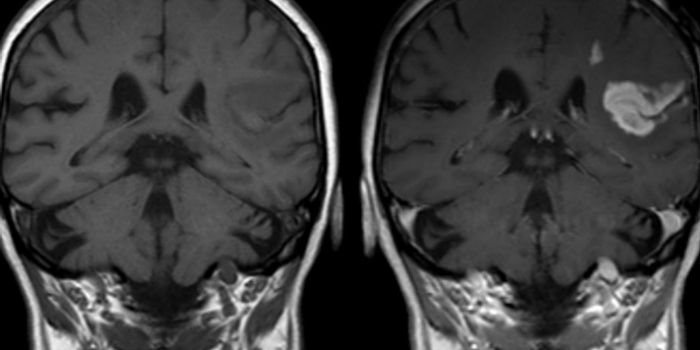

JUL 01, 2016CancerThe diagnosis of glioblastoma often bears one of the grimmest prognosis for patients. But a new research discovery may o ...

MAR 23, 2016CancerIn a large drug screening trial, scientists identified a unique drug combination that is effective against the most aggr ...

DEC 17, 2015NeuroscienceGlioblastomas or GBMs are the most devastating kind of cancer tumor found in the central nervous system in adults. Tumor ...